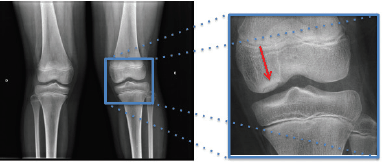

Considere a seguinte radiografia e assinale a alternativa que apresenta o diagnóstico mais provável.

A

Osteonecrose por hemoglobinopatia

B

Fratura por impactação

C

Sobreposição da patela

D

Fratura avulsiva

E

Osteocondrite Dissecante